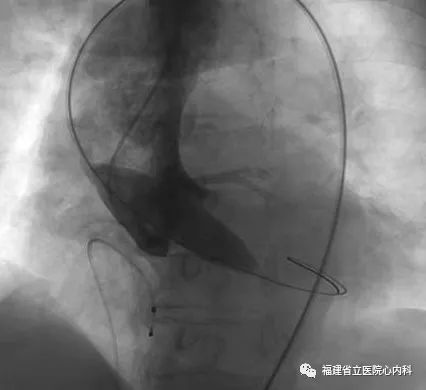

该病例主动脉瓣为功能性二叶瓣,瓣叶增厚且重度钙化,主动脉根部整体结构大需植入最大型号的人工瓣膜,患者升主动脉增宽且为横位心,增加了大瓣膜植入的难度,术者通过术前CT的精准评估,制定了对应的介入治疗策略,最终在术者稳当的控制下,Venus A- L32瓣膜精准地锚定在预期位置,术后患者症状明显改善。

瓣环

窦部

植入L32瓣膜